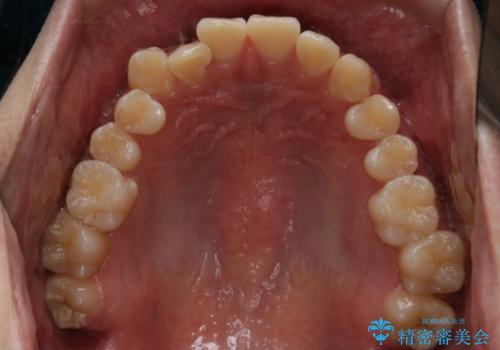

- 前歯のがたつきが気になるとご相談にいらした方です。左の奥歯の噛み合わせのズレも認められたため、インビザライン治療にて改善しました。

主訴である前歯のガタつきだけでなく、奥歯の噛み合わせからしっかり治療したため、治療期間が長めとなりました。患者様ご本人としては治療の途中で一時的にモチベーションが下がったこともあったようですが、最後まで頑張って続けて頂けたことで噛み合わせ及び見た目の改善を行うことが出来ました。